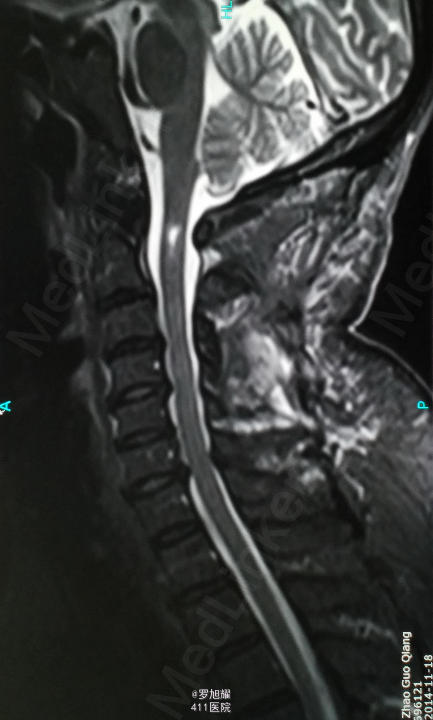

入院立即给与大剂量甲强龙冲击治疗,辅以甘露醇脱水消肿,兰索拉唑保护胃黏膜,腺苷钴胺恩经复营养神经,伤后10天复查MRI脊髓信号增高明显,两周后生命体征稳定,肢体感觉和肌力见部分恢复,行颈2椎弓根螺钉、颈3侧块钉内固定术,因神经压迫不明显未行椎板切除减压。 术后3月骨折线基本消失,患者感觉肌力几乎完全正常,右肩残留疼痛磁共振检查发现肩袖损伤,暂予局封治疗症状缓解。

该患者术后4月随访瘫痪症状完全消失,感觉正常,右侧肌力已经接近5级,但Mri随访T2加权像仍可见明显的脊髓高信号,但是影像学上脊髓变性和患者的症状没有明显的相关性,说明神经功能的代偿潜能还是非常巨大的,各位老师和同仁是否同意呢?